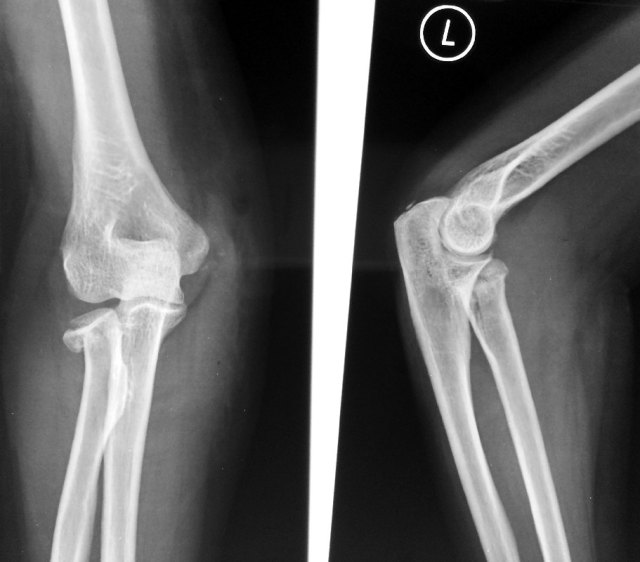

Radial Head Fractures

Radial head fractures are among the most common elbow fractures occurring in up to 20% of all elbow injuries.

30% have associated soft tissue or other bony injuries e..g. ulnar fractures

The patient will have pain and swelling of the affected elbow. Movement especially in forearm rotation (pronation and supination) are especially difficult and painful.